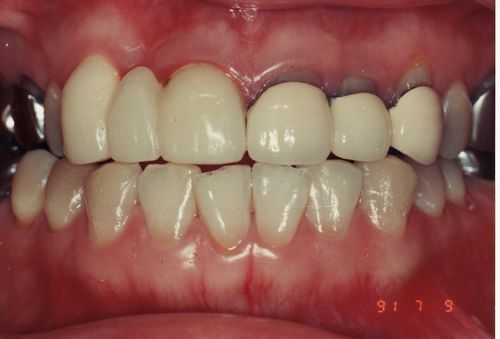

(術後)

審美歯科術後.jpg

上の前歯6本をメタルボンドCで修復しました。最終的な仕上がりにも非常に満足され、感謝されました。「少しでも長持ちさせるために歯ブラシの仕方を教えてください。」とおっしゃられていましたので、「何事にもはどほどが肝心です。大事にしたい気持ちはわかりますが、磨きすぎてかえって歯肉が下がってしまうこともありますので、磨きすぎだけには気をつけて下さい。」とお伝えしました。

本人も合っていないのは気付いていたようなのですが、人工的なものではこの程度しか仕方がないと思っていたようです。もし同じような歯が入っていてあきらめている人がいるとするならば、歯肉の状態さえよければ、この程度まで直せます。是非一度ご相談下さい。(自費診療になります。症例によって値段が変わってきます。右上2番は専門用語でブリッジのダミー(ポンティック)と言います。歯のない状態で歯肉の上に乗っかっています。1番3番と繋がっていて両側の歯に支えられています。この右上2番も1本にカウントされます。この場合メタルボンドC1本8万円×6本=48万円。これ以外に保険診療分がかかります。)